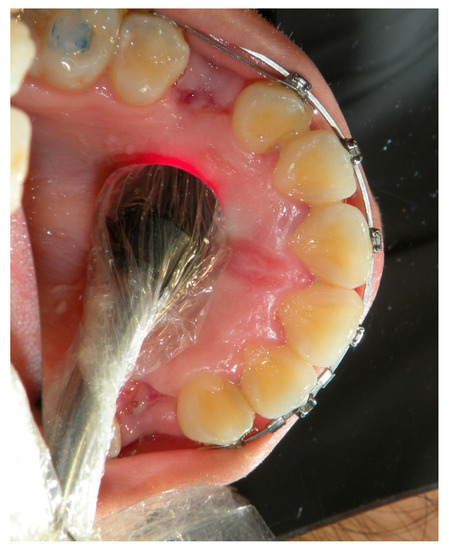

2.1.2. PBMT Protocol

| Step 1: Laser Application on Vestibular Side | Step 2: Laser Application on Palatal Side |

| Apical third (10 s) | Apical third (10 s) |

| Medium third (10 s) | Medium third (10 s) |

| Cervical third (10 s) | Cervical third (10 s) |